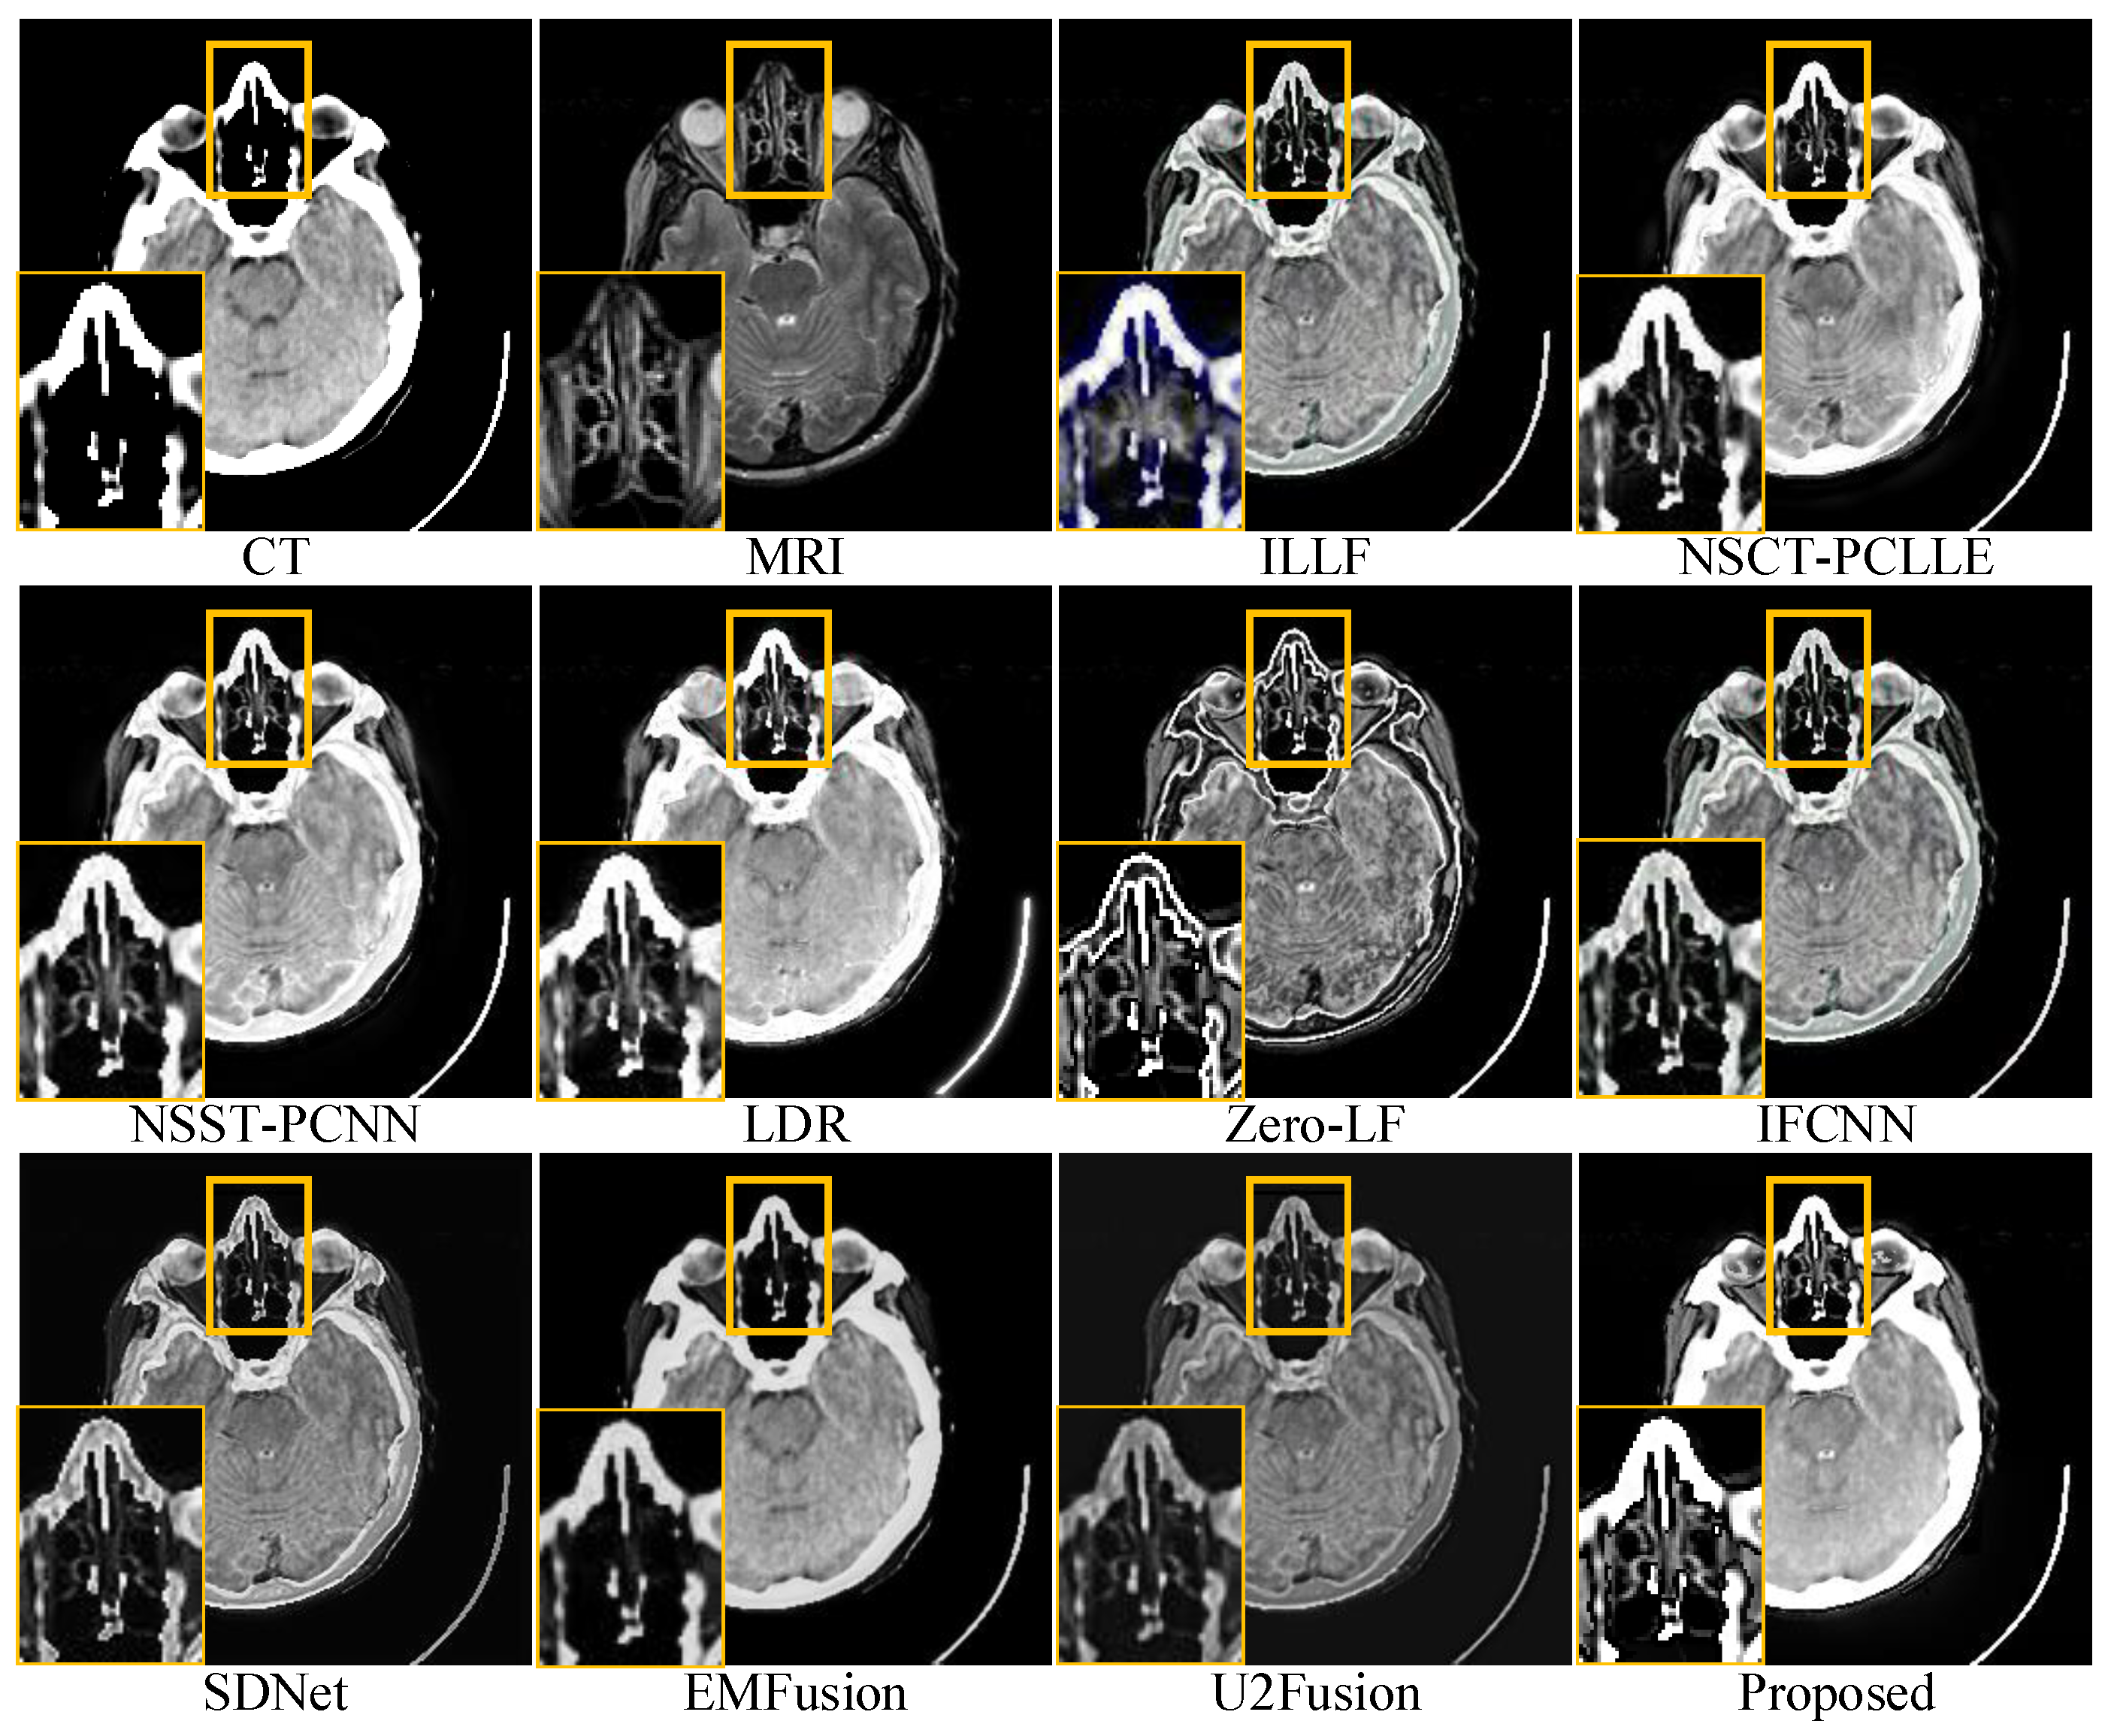

For conciseness, we have only shown the results of three sets of images in the subjective evaluation. Figure 5, Figure 6 and Figure 7 show the fusion results of different types of medical images obtained by different image fusion algorithms.

Figure 5.

Comparison of performances of various methods on computed tomography magnetic resonance imaging (CT-MRI) source images. For a clear comparison, we select a same region (i.e., the yellow box) in each image and zoom in it in the bottom left corner.

The fusion results of the different methods on CT-MRI medical images are shown in Figure 5. The local areas are marked by colored rectangles, which are enlarged in the lower left corners for better comparison. All the methods retained the main information and features, as shown in Figure 5; however, there were still significant differences regarding the features. ILLF showed color distortion, which led to the introduction of speckles in the fusion results. Zero-LF, IFCNN, SDNet, EMFusion, and U2Fusion could not completely retain the energy in the CT images, leading to low brightness and contrast in the fusion results. Second, NSCT-PCLLE, NSST-PCNN, LDR, SDNet, EMFusion, and U2Fusion were unable to retain the detail information in the MRI images (yellow part of the magnification area). Figure 5 shows that the proposed method outperformed the other methods in terms of the energy retention of CT-MRI medical-source images. It also successfully preserved information such as the details and structures in the source images without artifacts and brightness distortion.